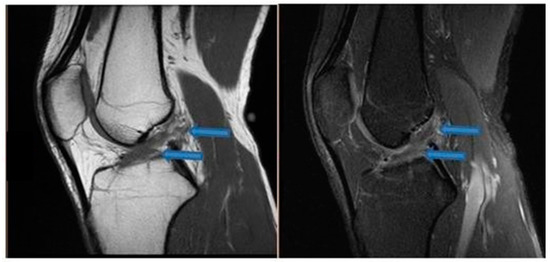

| 9 November 2020 | MRI scans demonstrating signs of partial ACL healing |

| 14 August 2021 | MRI scans demonstrating signs of complete ACL healing |

| 24 December 2021 | MRI scans confirming signs of complete ACL, MCL and medial meniscus healing |